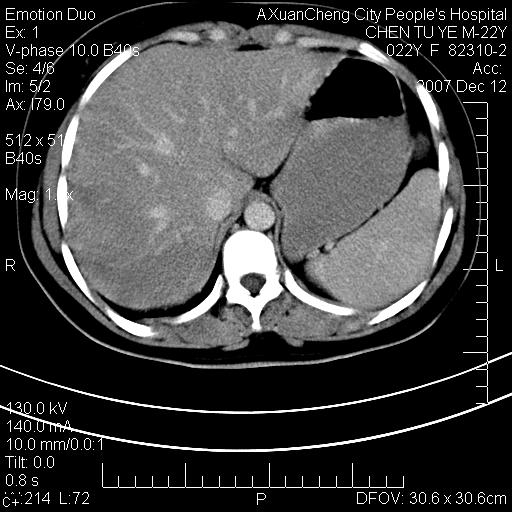

超声提示肝右前叶占位,约2.5cm.

各位战友看看病灶在什么地方,可是右前叶进肝裂部低密度影,平扫ct值约10以下,增强后增高明显

肝圆韧带

1 脾大,慢性肝损伤. 2 肝脏脂肪侵润.  3 你所指的部位疑点,我没看出有问题.

脂肪肝.楼主所指部位不考虑异常,为肝圆韧带影.

不均匀脂肪浸润,版主所说的病灶为肝园韧带服着点。

考虑肝圆韧带。